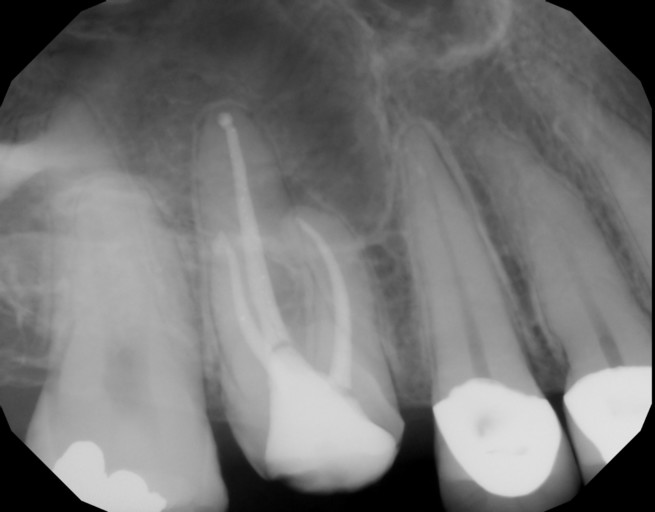

Hi, I will have my upper left premolar extracted tomorrow due to an abscess. I was wondering why an antibiotic cannot be injected on the site and treat the infection around the root instead of removing the tooth. I will be left with a huge gap because my molar was wrongly extracted since the dentist assumed the pain was coming from a sensitive nerve (it was alive) last year but now it seems the problem was the premolar which is with a crown and had a root canal. They also performed my sinus (OC) and now the risk of happening the same is very high. I cannot see a specialist who will do re-root canal to try to save my tooth. Please can you help me with an advice how to preserve my tooth? Why injecting antibiotics is not usually considered? Is it because the bacteria make a biofilm and cannot be targeted? Thank you!